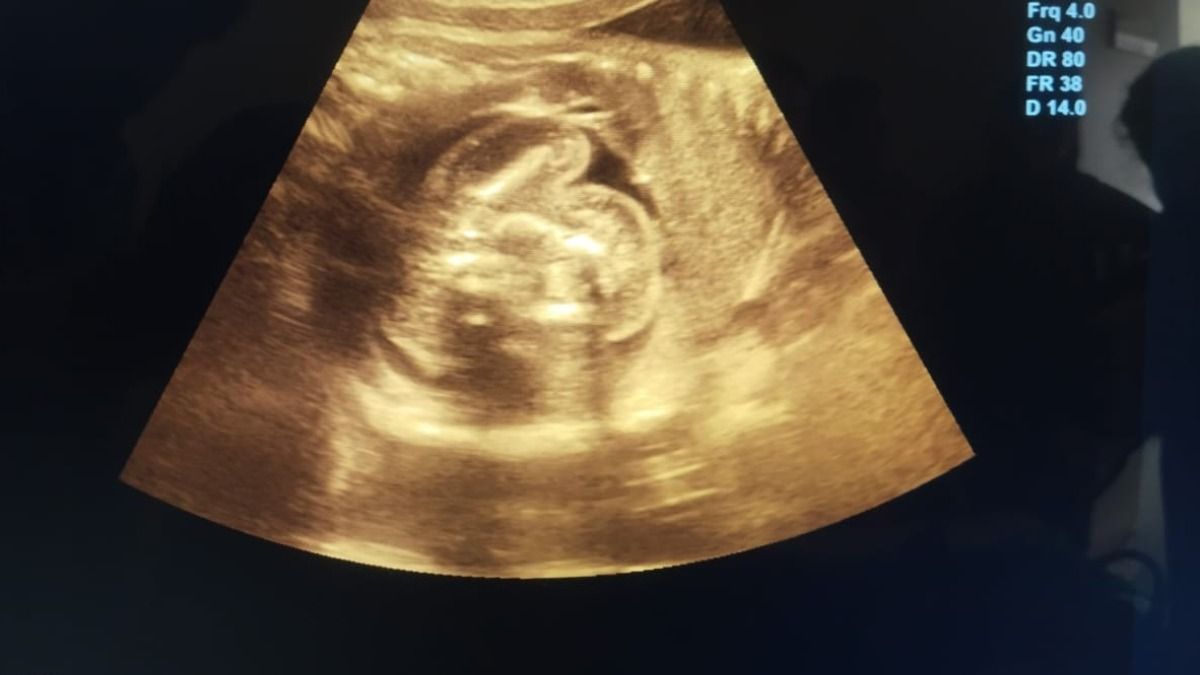

बुलंदशहर में महिला के गर्भाशय की जगह लीवर में पल रहा था बच्चा ,जांच हुई तो डॉक्टरों के उड़े होश

बुलंदशहर की एक महिला के लीवर में 12 हफ्ते का भ्रूण मिला, जो मेडिकल जगत के लिए हैरान कर देने वाला मामला है. डॉक्टरों के मुताबिक यह भारत में अपनी तरह का पहला और दुनिया में बेहद दुर्लभ केस है।

एमआरआई रिपोर्ट में पता चला की महिला प्रग्नेंट तो हैं लेकिन उसका गर्भाशय यानी यूट्रस खाली है. हैरानी की बात ये थी कि 12 हफ्ते का गर्भ उसके गर्भाशय में नहीं, बल्कि लीवर के दाहिने हिस्से में पल रहा था. गर्भ में धड़कन भी थी, यानी भ्रूण पूरी तरह से ज़िंदा था.

इस मामले की पुष्टि करने वाले डॉक्टर के.के. गुप्ता, जो एक रेडियोलॉजिस्ट हैं ने कहा कि इतने सालों के वो इस काम को कर रहे हैं लेकिन उनके करियर में ऐसा केस पहली बार आया है. पूरी दुनिया में अभी तक ऐसे सिर्फ 18 केस ही सामने आए हैं और भारत में यह पहला मामला हो सकता है.